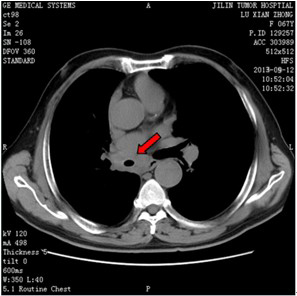

双锁骨上淋巴结肿大分别达6.0cm和4.0cm,质硬如骨骼、固定、无压痛,ECT示左肩胛骨、右股骨中下段骨代谢异常活跃,胸部CT发现两肺转移。

治疗3周期后双锁骨上淋巴结明显缩小,4周期后双锁骨上淋巴结接近消失,两肺转移灶明显减少或缩小,左肩关节疼痛消失,声音嘶哑无变化。疗效评价为部分缓解(PR)。